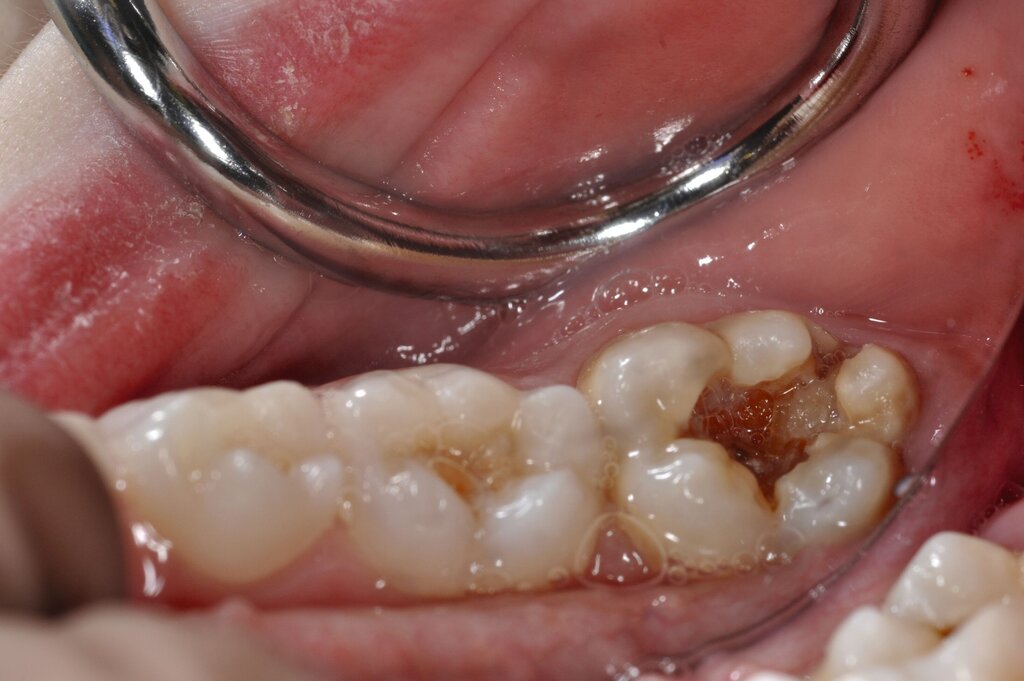

Die temporäre Therapie C (kurzfristig)

Die Therapie C hat das Ziel, MIH-Zähne vorübergehend zu versorgen, bis der vollständige Durchbruch der Zähne eine adhäsive Restauration ermöglicht, um die hypersensiblen Zähne zu desensibilisieren oder/und die Mitarbeit für die weitere Behandlung aufzubauen. Vor dem Hintergrund des erhöhten Kariesrisikos dieser Zähne (Abbildung 2) muss durch die Maßnahmen eine Kariesprogression vermieden werden.

Als mögliche Maßnahme steht eine Abdeckung der Defekte mittels konventioneller Glasionomerzemente (GIZ) zur Verfügung. Vorteil der Materialien ist die schnelle und einfache Applikation der Zemente. Bei MIH-Molaren werden diese in der Regel mittels der sogenannten ART-Technik (Atraumatic Restorative Treatment) eingesetzt [Grossi et al., 2018]. Dabei wird lediglich mit einem Handinstrument die Zahnoberfläche gereinigt und gegebenenfalls Karies exkaviert. Anschließend wird die Kavität unter relativer Trockenlegung mit dem GIZ aufgefüllt.

Der Vorteil der Methode ist, dass die betroffenen Zähne auch ohne Lokalanästhesie und Präparation versorgt werden können. Die temporäre Versorgung ermöglicht es, die Patienten an die zahnärztliche Behandlung zu gewöhnen. Häufig führt diese temporäre Versorgung auch zu einer Reduktion der Hypersensitivität der MIH-Zähne. Nachteil der GIZ-Versorgung ist das Risiko einer Füllungsfraktur oder eines vollständigen Verlusts der Füllung (Abbildung 4). Aktuelle Erhebungen bestätigen eine Erfolgsrate von über 80 Prozent nach einem bis zwei Jahren [Durmus et al., 2021; Mahfouz et al., 2025].

Der Behandlungsfall (Abbildung 4d) veranschaulicht die Schwächen des Verfahrens. Wird das Angebot der regelmäßigen Kontrollen nicht wahrgenommen, so droht bei Verlust der Füllung die Kariesprogression. In dem vorliegenden Fall konnte jedoch eine endodontische Maßnahme vermieden und durch die selektive Kariesentfernung die Zahnhartsubstanz weitestgehend erhalten werden.